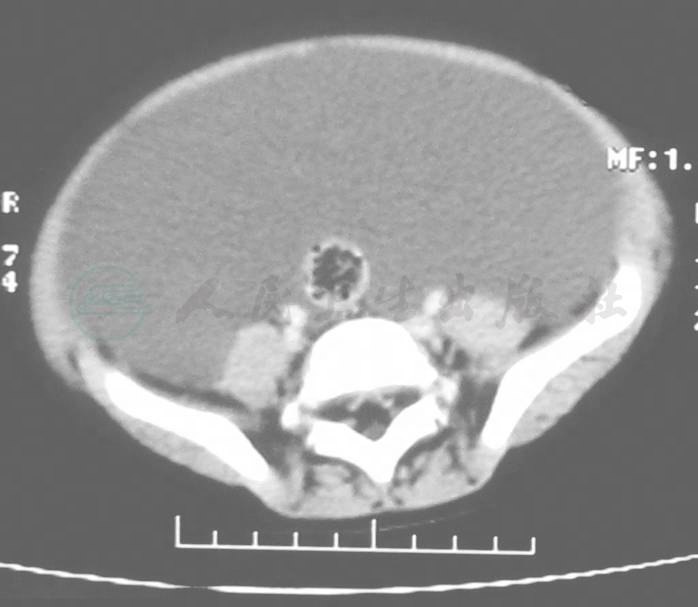

给予术前检查后,再行CT检查,CT报告仍提示:大量腹腔积液(图1~图2),但是再次超声检查提示腹腔内包裹性腹腔积液。

图1 上中腹部CT增强片

图2 下腹部CT增强片